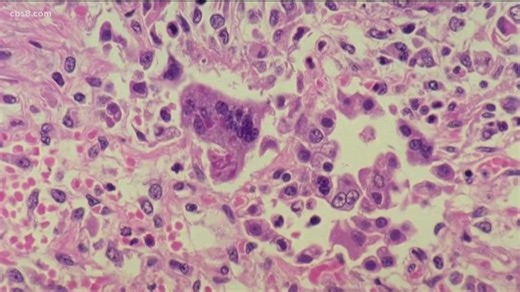

Former Sharp Hospital doctor claims corroboration of secret rec

…

2019年4月9日

cbs8.com